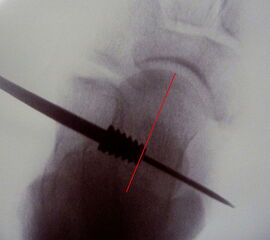

• Sehr sicheres Verfahren sobald der Führungsdraht im Sinus tarsi platziert ist. Das zugehörige Instrumentarium, alle Probeimplatate und auch das endgültige Implantat sind kanüliert und werden stets über diesen Guidepin geführt.

Abbildung 1

• ProStop Implantationssieb von Arthrex mit Führungspin, Probeimplantaten in aufsteigender Größe und lasermarkiertem Eindrehinstrument mit Handgriff (Abb.1).

• Bildverstärker.